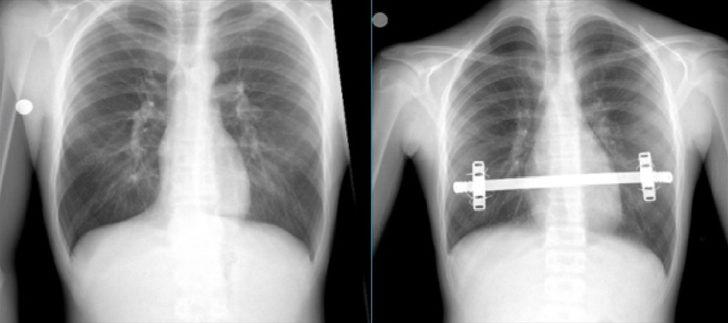

Trabzon'da, halk arasında "kunduracı göğsü" olarak bilinen Pektus Ekscavatum hastalığı ile mücadele eden Hamza Suiçmez, 2 saat süren ameliyatın ardından sağlığına kavuştu.

Suiçmez'e, yapılan tetkikler neticesinde halk arasında "kunduracı göğsü" olarak da bilinen Pektus Ekscavatum hastalığı tanısı konuldu.

Erken yorulma ve çarpıntı şikayetlerinin, içeri doğru basık olan iman tahtasının kalp üzerine baskı yapmasından kaynaklandığı anlaşılan hasta, KTÜ Farabi Hastanesi Başhekimi ve Göğüs Cerrahisi Anabilim Dalı Başkanı Prof. Dr. Celal Tekinbaş ve ekibi tarafından ameliyat edildi.

"Kapalı kunduracı göğsü ameliyatı (NUSS)" uygulanmasının ardından sağlığına kavuşan Suiçmez, şikayetlerinin artık olmadığını ve en önemlisi de kendisini daha özgüvenli ve sosyal hissettiğini belirtti.